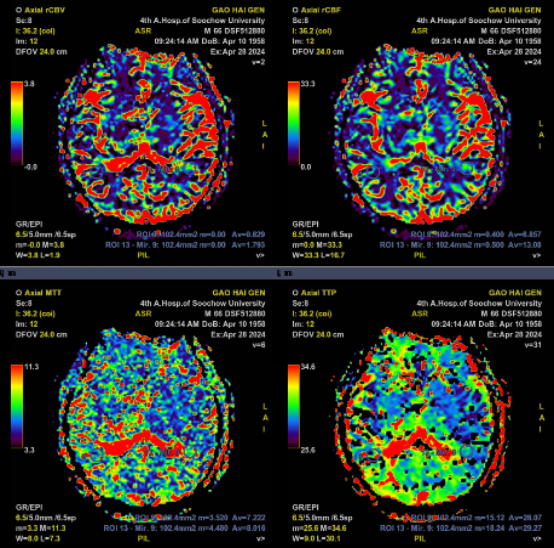

CTA+CTP:右侧大脑中动脉水平段(R-M1)管腔完全闭塞;右侧额顶颞叶缺血性灌注异常

患者再次入院后,郝永岗教授等专家合作完成苏州市首例术中磁共振指导下的症状性颅内动脉狭窄支架植入术。此次手术充分利用我院复合手术室(DSA+MRI双杂交)的优势,有效提高了手术的安全性和有效性。术后即刻行MRI-PWI显示:责任血管供血区血流灌注较前明显改善,提示支架精准定位释放。

术前PWI:右侧岛叶、颞叶、右侧脑室旁及放射冠区CBF、CBV减低,MTT、TTP较对侧延长